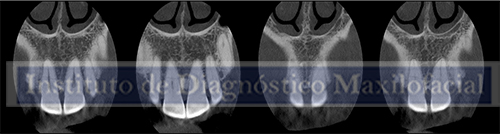

Así mismo se evidencia en la tomografía localizada un trazo de fractura horizontal a nivel de tercio medio radicular sin desplazamiento de fragmento.

Fractura radicular de la pieza 1.1